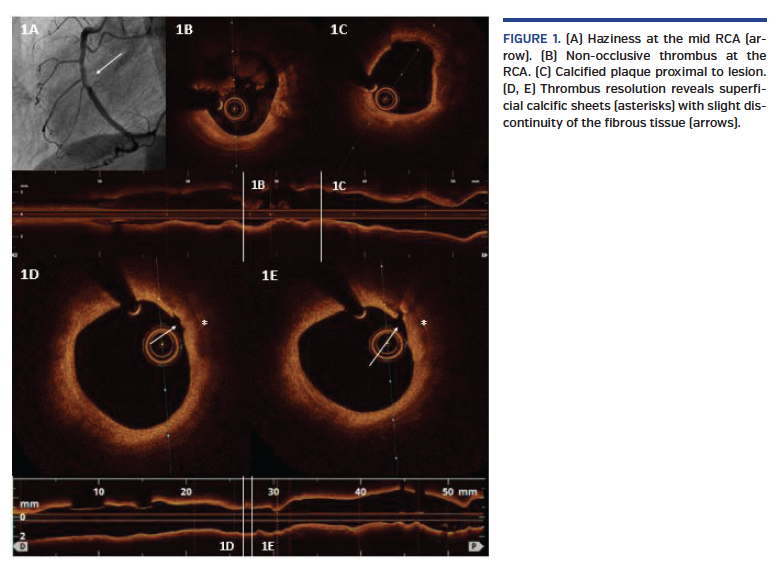

We present the case of a 63-year-old woman, former smoker, transferred to the catheterization laboratory for primary percutaneous coronary intervention in the midst of anterior ST-segment elevation myocardial infarction. Coronary angiography showed acute total occlusion of the proximal left anterior descending (LAD) (Video 1). After the guidewire passed through the distal LAD, TIMI-3 flow revealed severe proximal stenosis, which was treated with an everolimus-eluting stent with good outcome (Video 2). Afterward, angiographic haziness was recognized at the mid right coronary artery (RCA) (Figure 1A). Optical coherence tomography (OCT) exhibited non-occlusive thrombus (Figure 1B) and calcified plaques were observed proximal to the lesion (Figure 1C). Tirofiban perfusion was administered. After 10 days under dual-antiplatelet therapy (DAPT) with aspirin and prasugrel, OCT was repeated, displaying thrombus resolution with superficial calcific sheets (SCS) (Figures 1D and 1E) and minimal disruption of overlying fibrous tissue (Figure 1D-E: arrows) without compromise of the luminal area. Prolonged DAPT was recommended.

SCS has been implicated recently in the pathogenesis of acute coronary syndromes, and could have caused the acute RCA thrombosis in our patient. The underlying mechanism seems to be different from eruptive calcified nodules, and different theories have been speculated. OCT was useful to characterize in vivo SCS and exclude other causes of acute coronary syndromes, such as plaque erosion. Nevertheless, the management and potential prognostic and clinical implications of this type of calcified plaque are not clear, so further investigation needs to be done.